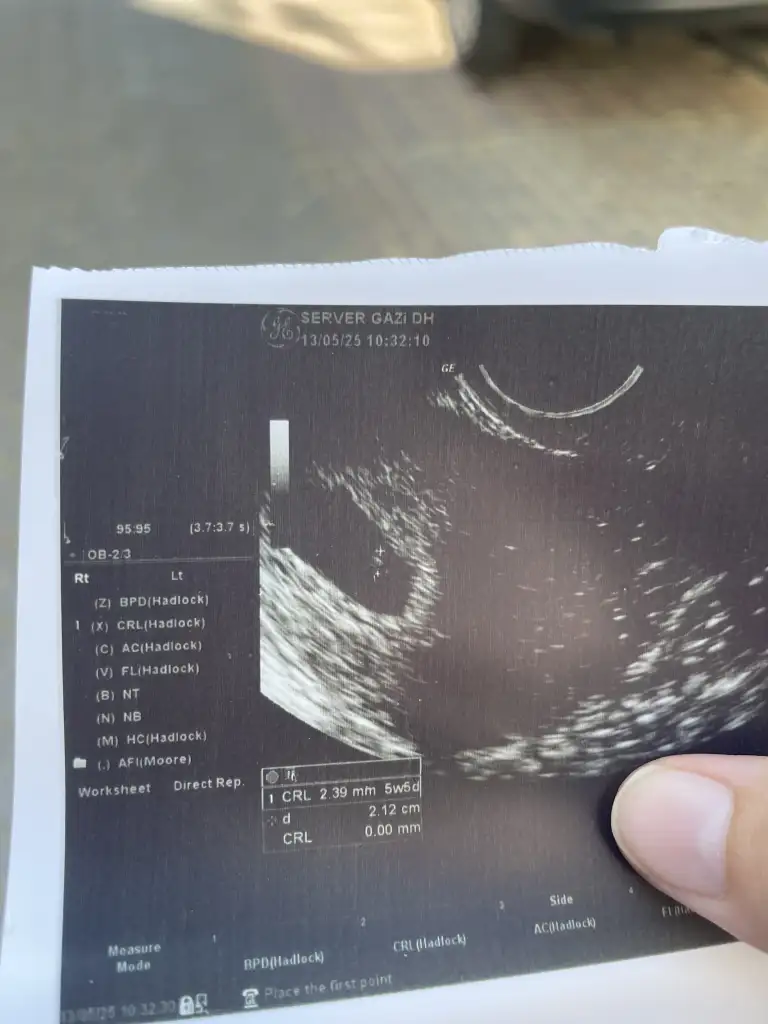

Aşkım beni bu kadar yakınlaştırmadı belki ondandır ama dedi içinde bebek var

Bilemedim ki aşko ya ekrandan gördüm bende kalp atışlarını yanıp sönüyorduAşkım beni bu kadar yakınlaştırmadı belki ondandır ama dedi içinde bebek var